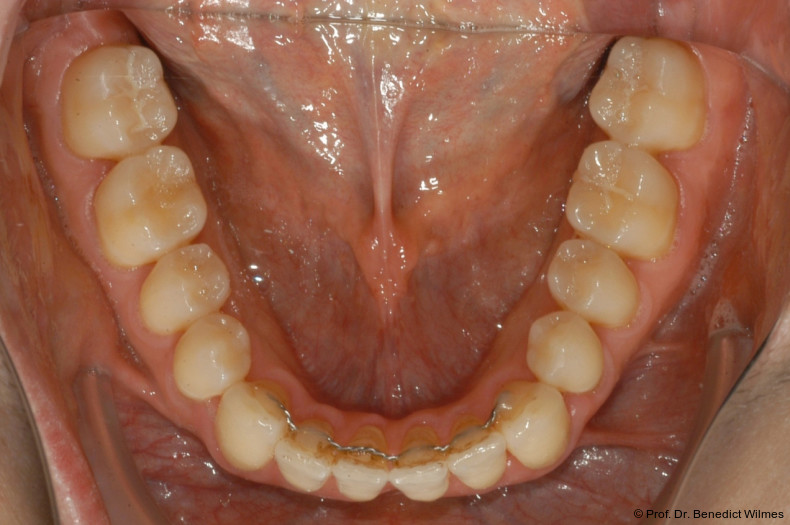

Nach Abschluss der kieferorthopädischen Pfeilerverteilung wurden zwei Miniimplantate in Regio 3er inseriert (2 x 13 mm). Nach Herstellung im Labor wurden Kronen auf den Miniimplantaten aufgeschraubt (Abb. 13+16a–d). Auch hier wurde darauf geachtet, dass die Kronen aus der Okklusion geschliffen wurden (Abb. 14). Bei den Nachkontrollen zeigten sich ebenfalls stabile Miniimplantate und ein entzündungsfreies Implantatlager ohne erkennbare Atrophie des Knochens (Abb. 15 und 16a–d).